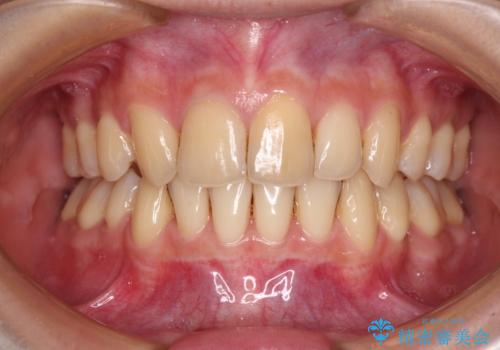

ふっくらとした口元を改善したい 目立たないワイヤー装置による抜歯矯正

担当医 藤巻太一朗